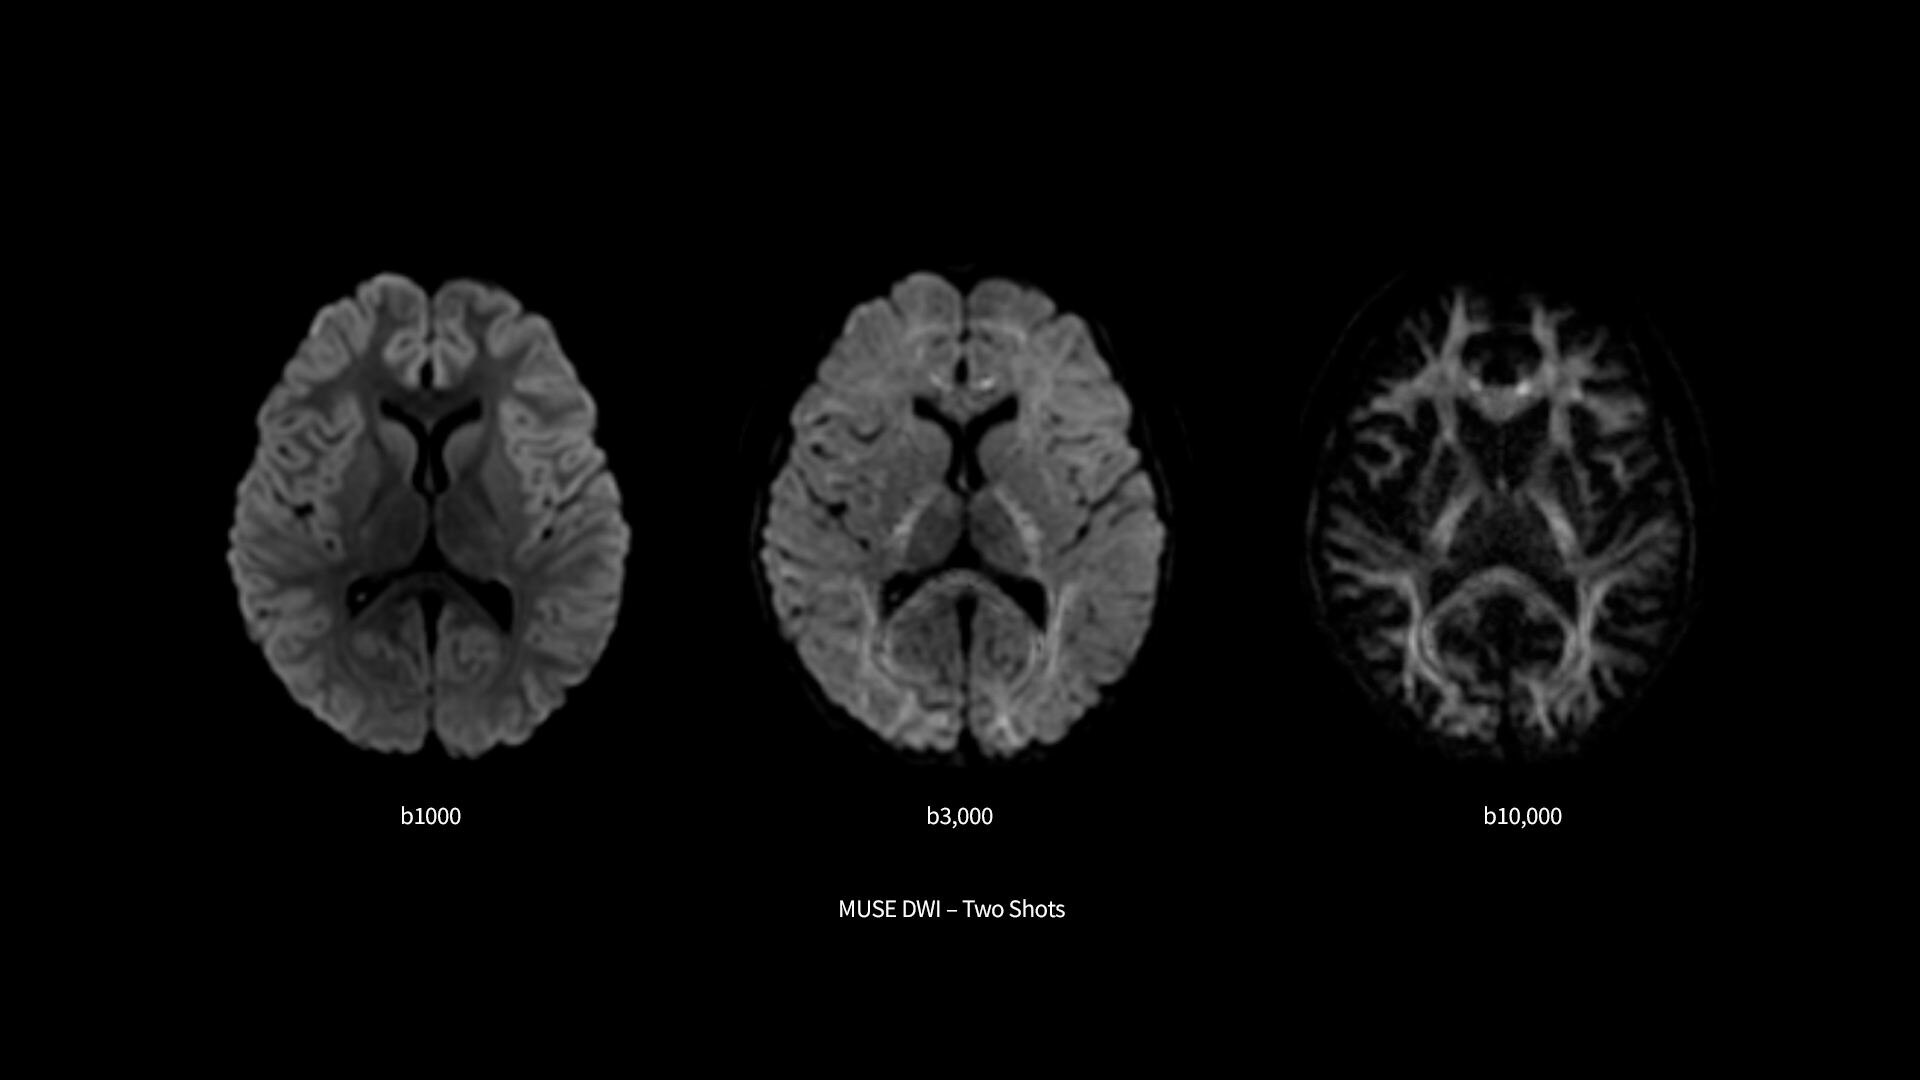

Revolutionary, deep-learning-based reconstruction techniques such as AIR™ Recon DL provide sharper, clearer, and accurate images

​SIGNA Premier supports the most demanding applications, such as Connectome-type studies that require Ultra-short TE diffusion imaging and high-resolution resting state fMRI. While it is a pioneering MRI system for cutting-edge research, it offers all the features needed to deliver routine clinical throughput. This includes delivering high end diagnostic image quality while ensuring the highest level of patient comfort.​

Pin-sharp image quality and exceptional speed with AIR Recon DL and Sonic DL​

Experience pin-sharp precision and remarkable speed with a 3T SIGNA Premier MRI scanner, coupled with AIR Recon DL and Sonic DL™.